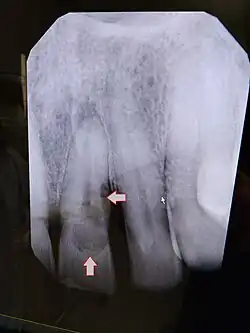

![]() Resorción externa incisivo central 21 | ||